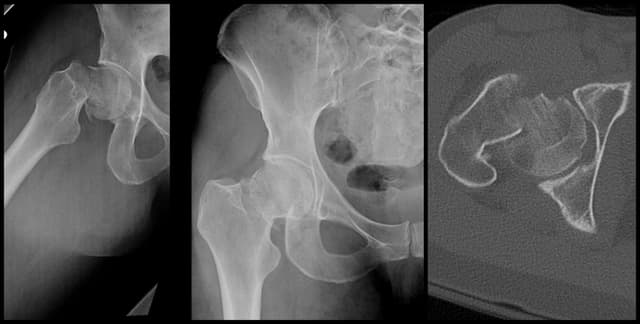

Femoral Neck ORIF

Pre-op